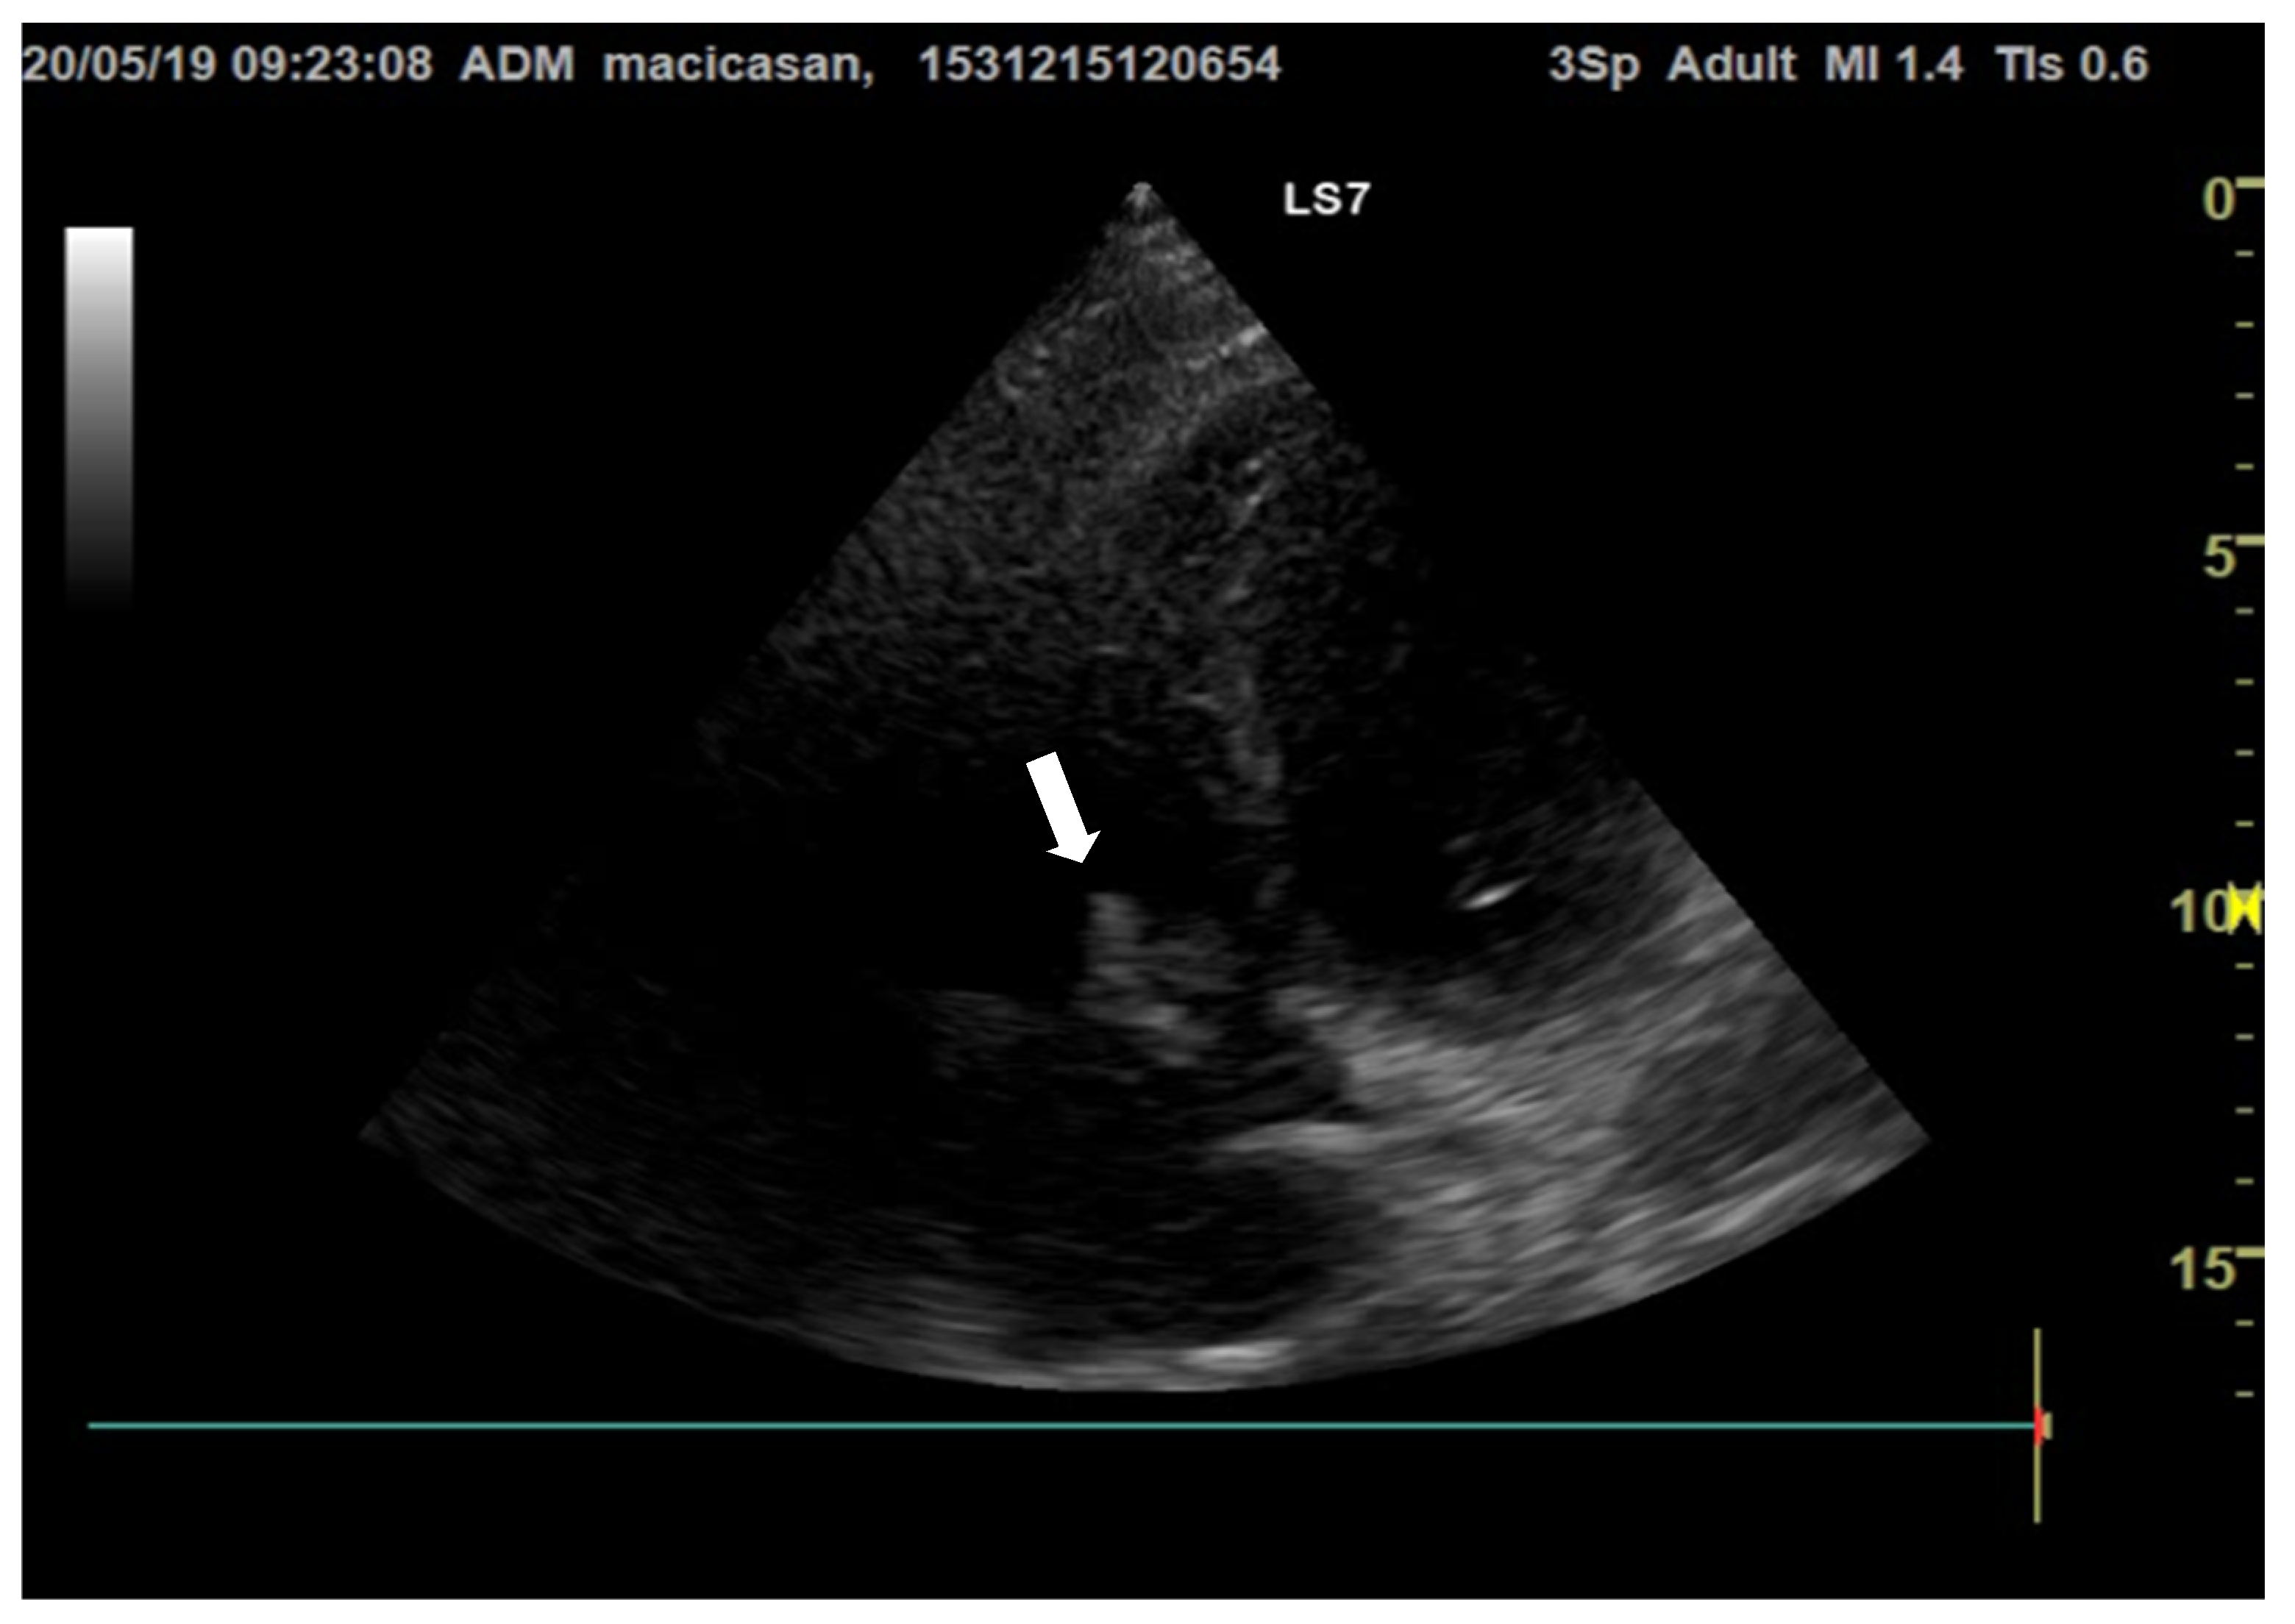

Doppler echocardiography showed a non-dilated left ventricle (LV—55/47 mm), grade III aortic insufficiency with a jet that hit the anterior mitral valve, mobile hyperechoic mass located on the aortic valve (3.5/0.95 cm) and on the tricuspid valve (2.5/1.4 cm), grade II tricuspid insufficiency, moderate secondary pulmonary hypertension (PAPs—50 mmHg), a slightly dilated right ventricle (40 mm sub tricuspid), TAPSE of 22 mm, EF of 50%, and free pericardium (Figure 2 and Figure 3).

Figure 3.

Transthoracic echocardiography, long axis parasternal section, reveals hyperechogenic vegetations on the aortic valves (the white arrow is indicating the vegetation on the aortic valve).